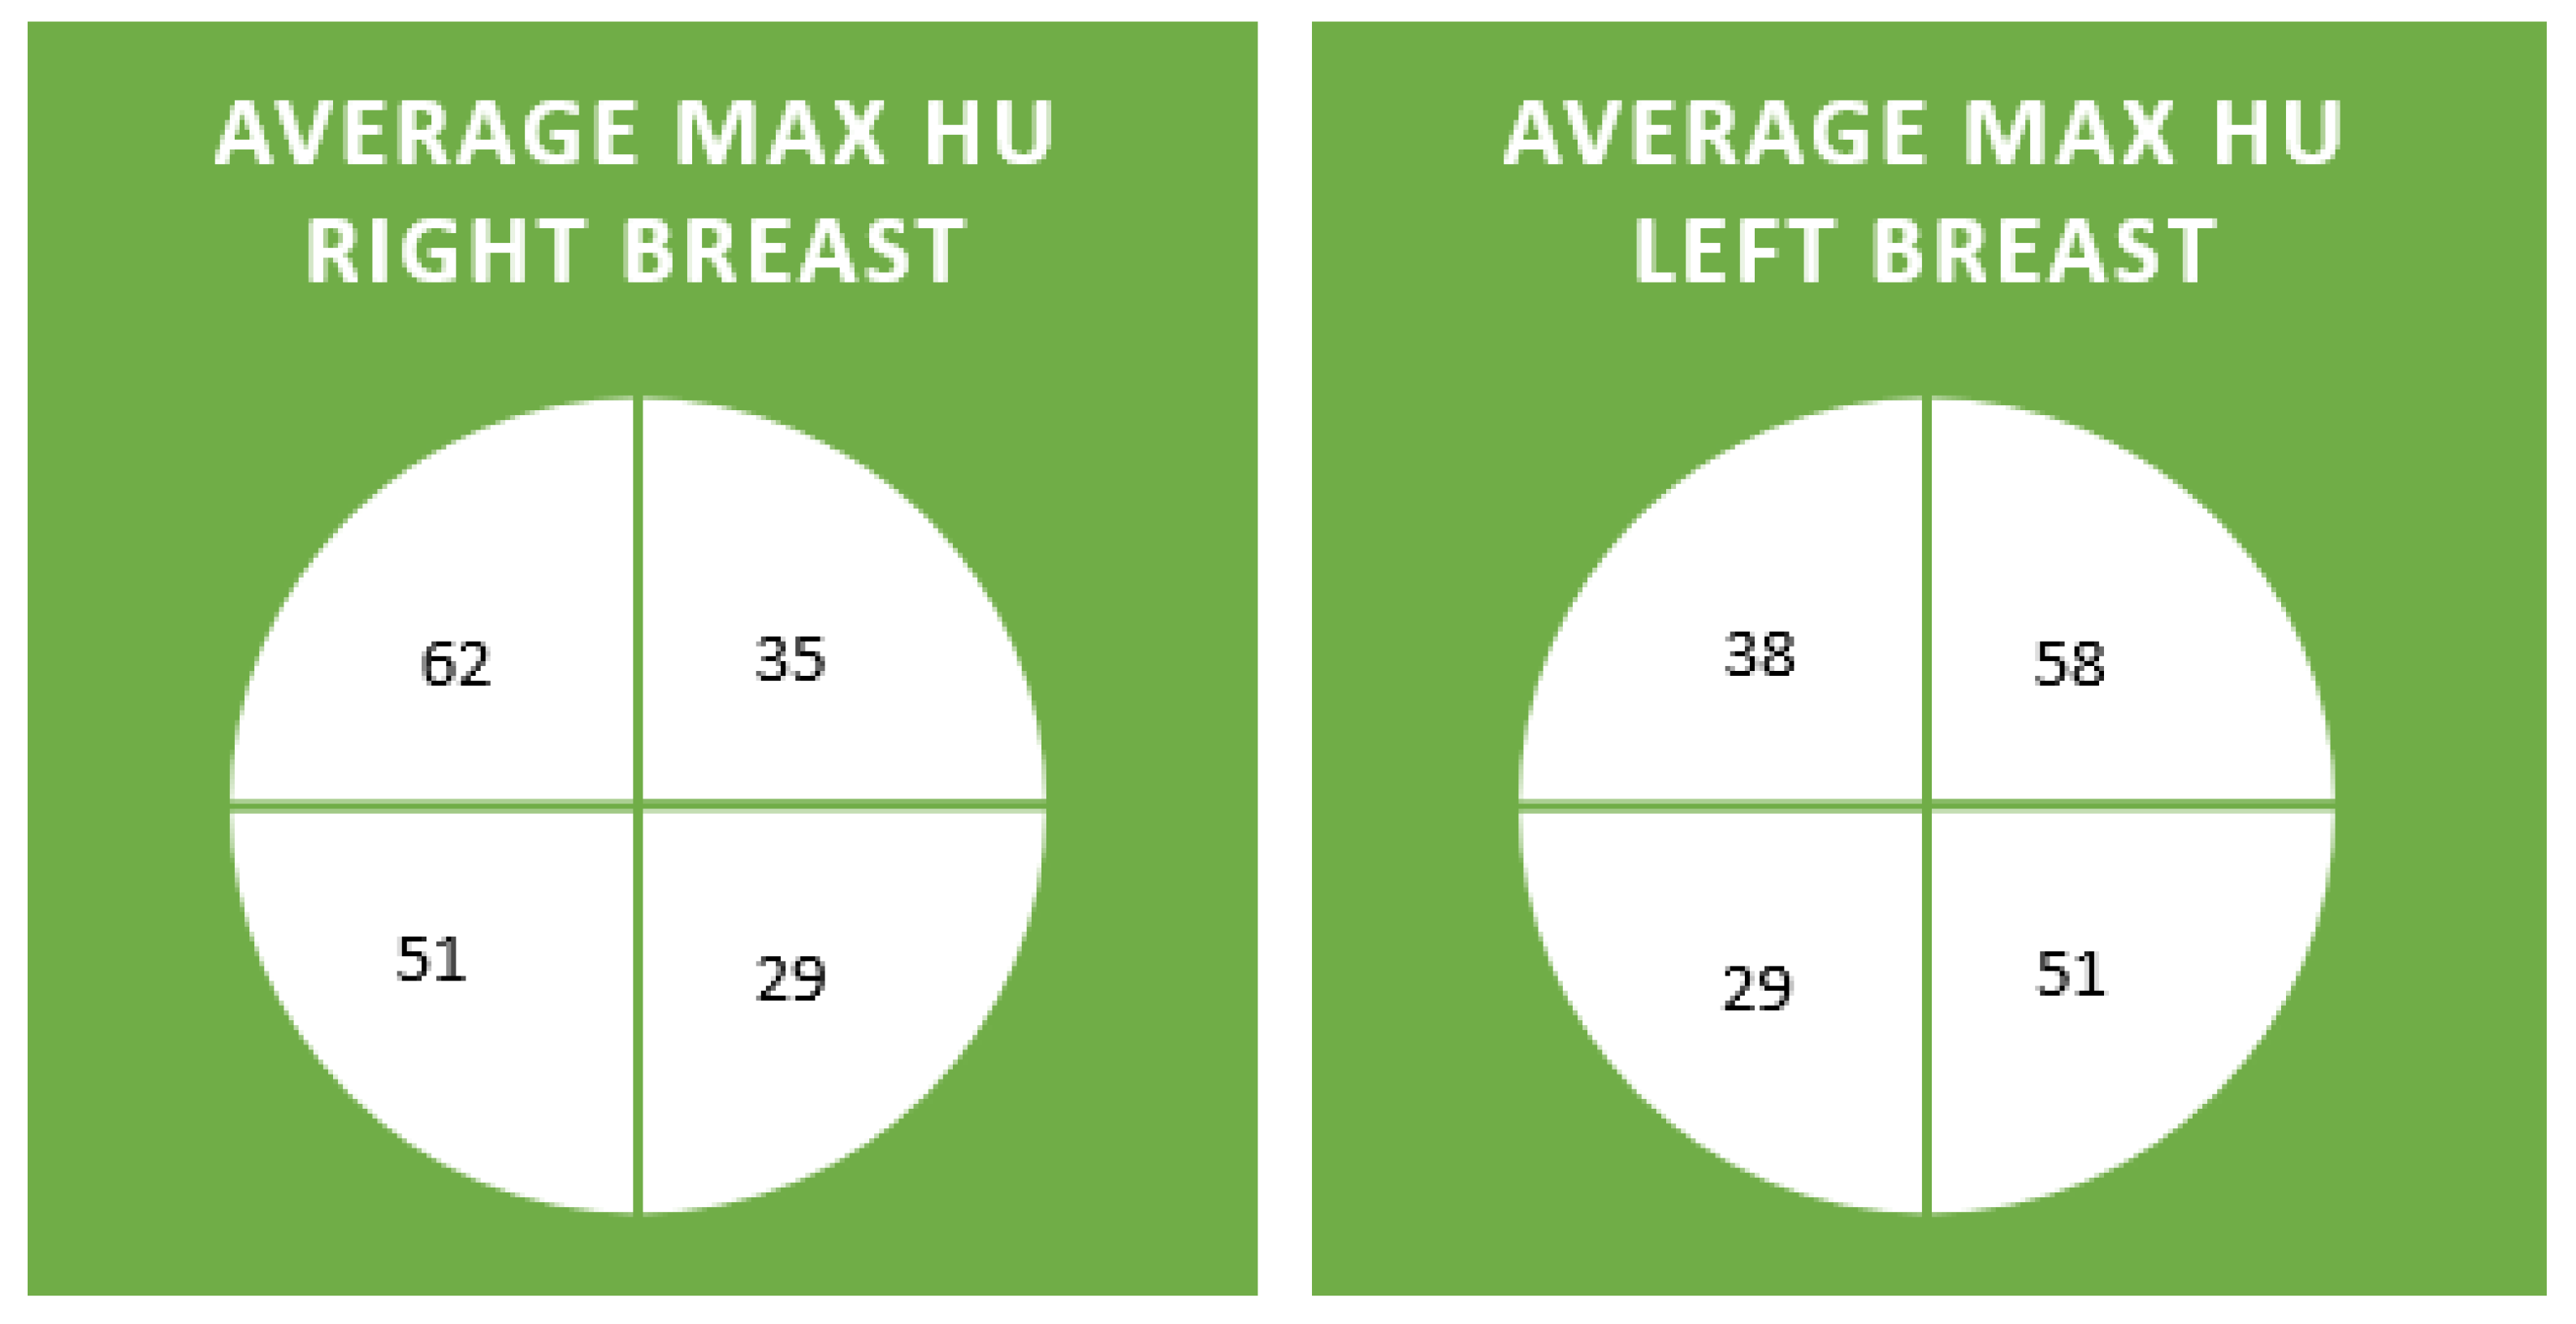

| RUO Max | 54 (35–74) | 68 (35–111) | 62 (26–99) | 59 (29–97) | 71 (36–204) | 58 (31–101) | 63 (36–106) |

| LUO Max | 44 (13–71) | 62 (44–79) | 58 (16–86) | 47 (27–84) | 78 (19–195) | 57 (36–85) | 52 (41–63) |

| RLO Max | 39 (21–64) | 57 (21–92) | 57 (34–94) | 60 (29–112) | 45 (22–76) | 47 (18–104) | 53 (43–60) |

| LLO Max | 40 (−17–62) | 62 (18–108) | 51 (4–78) | 40 (23–86) | 46 (7–72) | 44 (4–97) | 59 (35–73) |

| RUI Max | 40 (9–69) | 43 (1–91) | 33 (1–123) | 38 (−19–86) | 30 (-5–59) | 30 (−1–79) | 34 (7–95) |

| LUI Max | 45 (26–81) | 42 (18–70) | 34 (4–80) | 41 (11–84) | 32 (1–84) | 34 (12–80) | 35 (21–58) |

| RLI Max | 33 (5–47) | 36 (−15–81) | 21 (−10–58) | 27 (−14–71) | 18 (−22–46) | 32 (9–86) | 33 (12–60) |

| LLI Max | 24 (−10–101) | 46 (3–75) | 29 (4–55) | 32 (8–81) | 10 (−33–46) | 22 (−9–76) | 31 (4–63) |